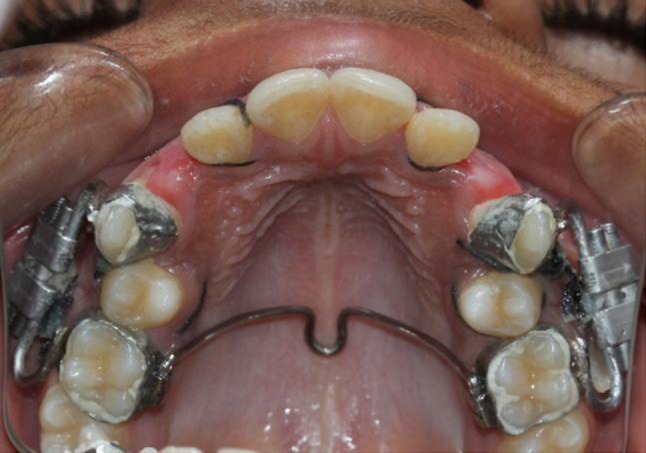

After the surgical procedure a custom-made intraoral distraction device was fabricated from a HYRAX expander (11 mm) (Fig. 8) which was trimmed, ground, and polished (Fig. 9). After preparation of the distractor screw, it was adapted on to the patient’s dental cast and soldering was completed on to the bands of the first molars and the canines that had been previously transferred to a dental cast (Fig. 10). Prior to soldering, the distractor screw was opened an amount equal to the mesio-distal width of the premolar to be extracted. Now intraoral distractors were cemented (Figs. 11, 12) and distraction was started in the PLD side on the same day. Distraction on the DAD side was started after a latency period of 3 days. The distraction device was activated twice a day at a rate of 0.8 mm per day. After completion of the distraction process, records were taken which included impressions, OPG and IOPAs and changes recorded (Figs. 13, 14, 15, 16, 17, 18). The patient was subjected to Pulp Vitality test and fixed mechanotherapy was started subsequently.

Fig. 11.

Distractors cemented bilaterally

Fig. 12.

Cemented distractors from occlusal view

Fig. 24.

First day of distraction

Fig. 25.

Tenth day of distraction

Fig. 26.

Fifteenth day of distraction

Fig. 27.

Completed distraction in both the sides